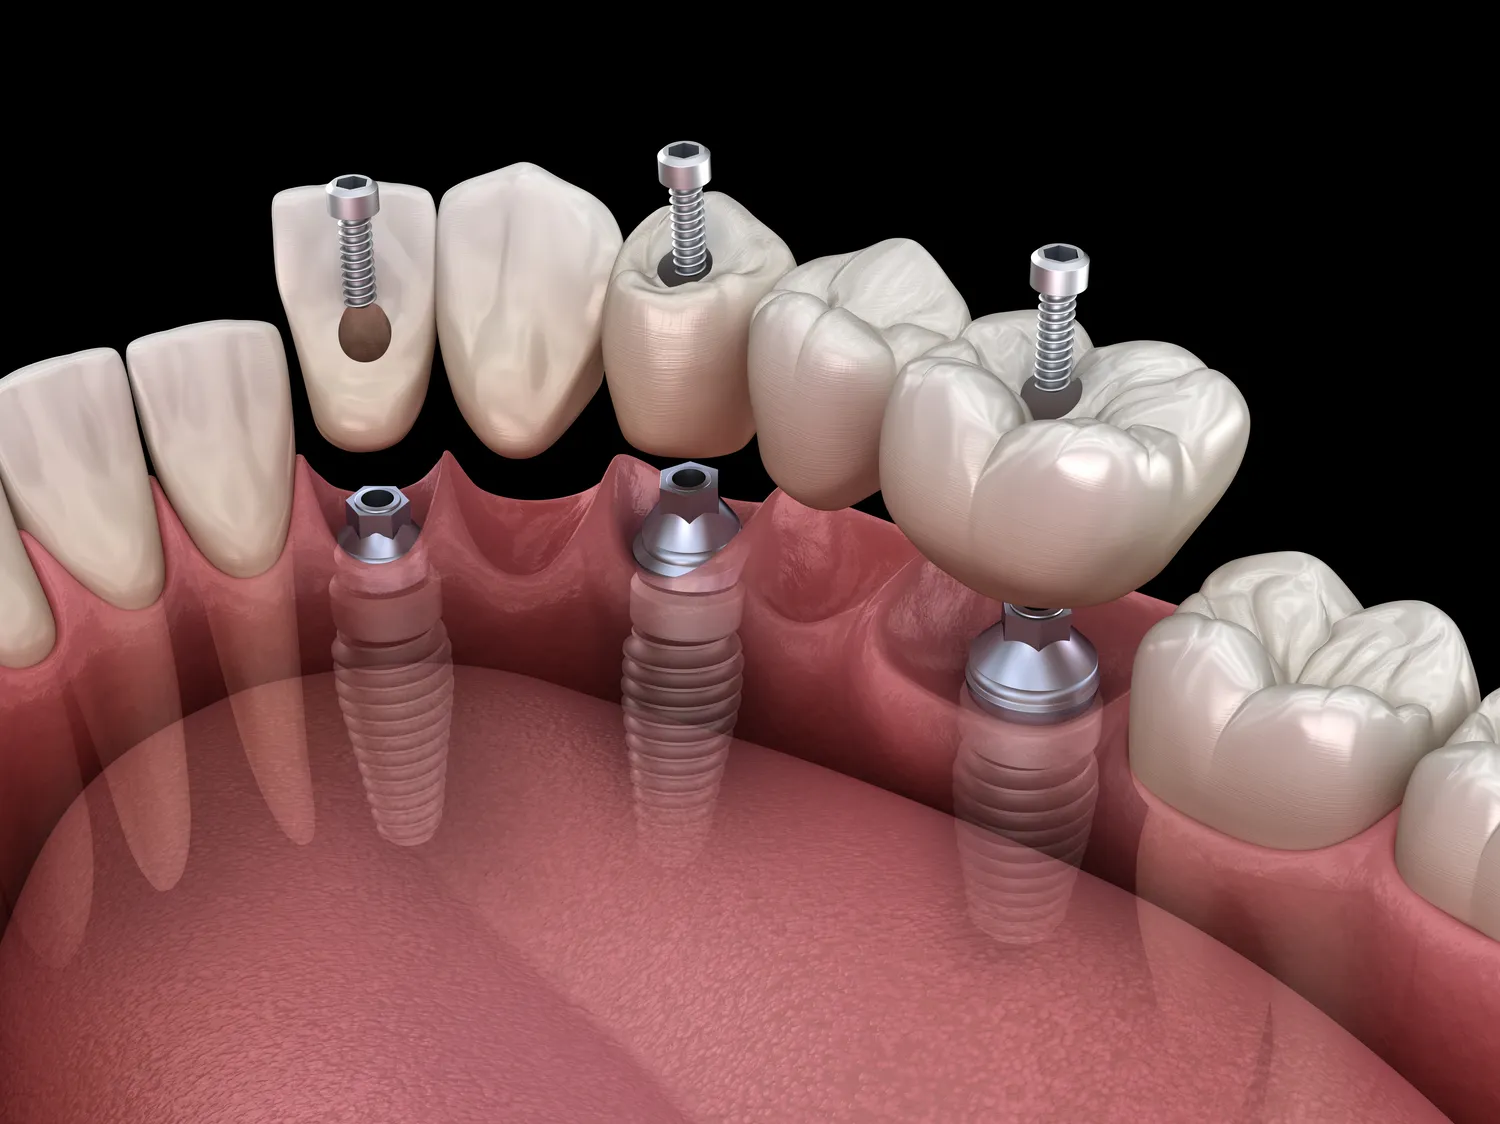

Leczenie kanałowe składa się z kilku kluczowych etapów, które mają na celu skuteczne usunięcie zakażonej miazgi oraz zabezpieczenie zęba przed dalszymi problemami. Pierwszym krokiem jest dokładna diagnostyka, która obejmuje zdjęcia rentgenowskie oraz ocenę stanu zęba przez dentystę. Następnie przystępuje się do znieczulenia pacjenta, co ma na celu zapewnienie mu komfortu podczas zabiegu. Po znieczuleniu dentysta wykonuje otwarcie komory zęba, aby uzyskać dostęp do miazgi. W tym momencie następuje usunięcie zakażonej tkanki oraz dokładne oczyszczenie kanałów korzeniowych. To kluczowy etap, ponieważ niewłaściwe oczyszczenie może prowadzić do nawrotu infekcji. Kolejnym krokiem jest wypełnienie kanałów specjalnym materiałem, który zapobiega ponownemu zakażeniu. Na koniec dentysta może założyć koronę lub inny rodzaj uzupełnienia protetycznego, aby przywrócić pełną funkcjonalność zęba. Każdy z tych etapów ma ogromne znaczenie dla skuteczności całego procesu leczenia oraz długoterminowej trwałości zęba.

W przypadku zakażenia miazgi zęba wiele osób zastanawia się nad alternatywami dla leczenia kanałowego. Choć leczenie kanałowe jest najskuteczniejszą metodą ratowania zębów w takich sytuacjach, istnieją inne opcje terapeutyczne, które mogą być rozważane w zależności od stopnia zaawansowania problemu oraz ogólnego stanu zdrowia pacjenta. Jedną z takich alternatyw jest ekstrakcja zęba, która polega na jego usunięciu w przypadku, gdy nie ma możliwości uratowania go poprzez leczenie kanałowe. Ekstrakcja może być konieczna w sytuacjach zaawansowanej infekcji lub poważnych uszkodzeń strukturalnych zęba. Inną opcją są zabiegi chirurgiczne, takie jak resekcja wierzchołka korzenia, które polegają na usunięciu części korzenia zęba wraz z zakażoną tkanką. Takie rozwiązania są jednak bardziej inwazyjne i wiążą się z dłuższym czasem rekonwalescencji oraz większym ryzykiem powikłań.